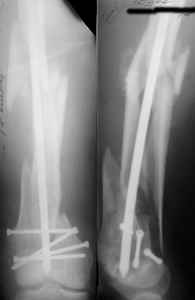

A new toy is more interesting and fashionable. And anyway it is not panacea, i have already seen presentations with LISS failures like the attached one presented by D.Seligson. And people also demonstrated incisions say that the method is not so LESS invasive as it supposed to be.